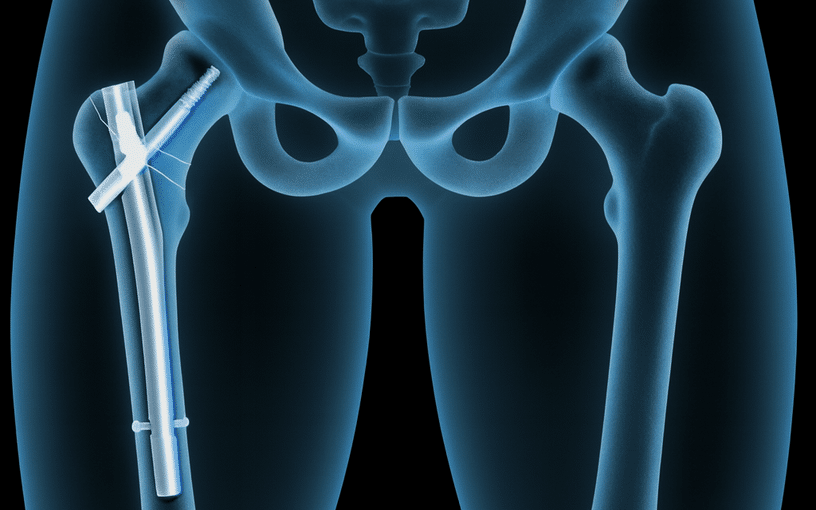

Prothèse totale de hanche (PTH)

La PTH est l'une des interventions chirurgicales les plus efficaces et les plus étudiées en orthopédie. Elle restaure une articulation indolore avec une durée de vie implantaire de 15 à 20 ans en moyenne.

Le choix de la voie d'abord (postérieure, antérieure de Hueter, ou de Röttinger) et du type d'implant (cimenté, non cimenté, hybride) est individualisé selon l'anatomie, l'âge et l'activité du patient.

Le protocole de Récupération Améliorée Après Chirurgie (RAAC) permet une mise en charge dès le jour de la chirurgie et un retour à domicile accéléré.